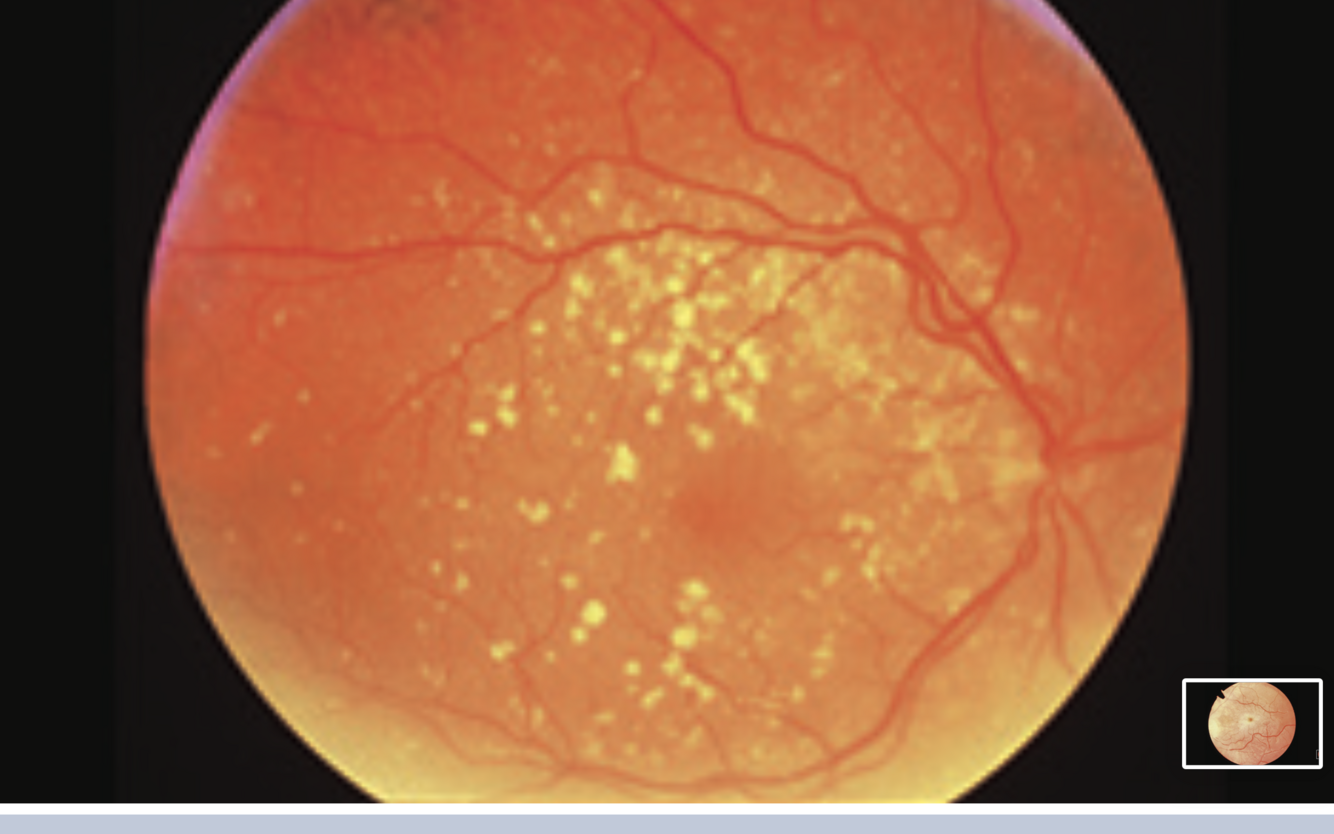

Pre-proliferative Diabetic Retinopathy

-cotton wool spots

- dot and blot haemorrhages